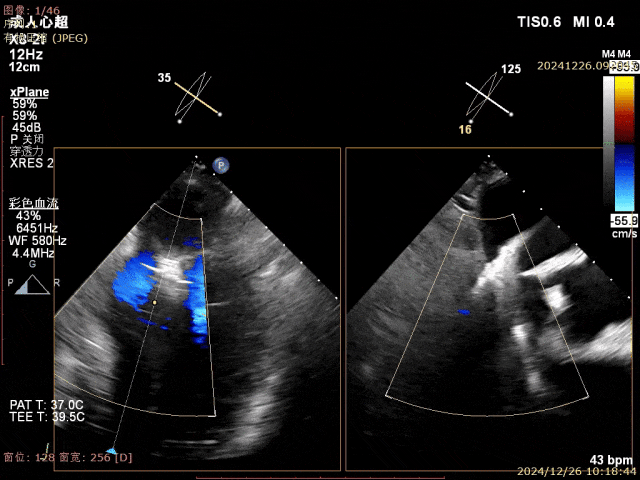

患者重度(4+)二尖瓣反流、并伴有P2区瓣叶脱垂及部分腱索断裂、且外科治疗风险极高,术中团队借助DragonFly™系统的高精度操控特点,精准解决了患者瓣叶脱垂问题,并仅凭一枚XW0612长宽二尖瓣夹即圆满完成手术。术后患者二尖瓣反流显著降低至微量,治疗效果满意。此次,TEER手术的成功,是大医一院结构性心脏病团队在二尖瓣微创介入治疗领域新的突破,将为更多瓣膜病患者提供一种更安全有效、更微创的治疗手段,从而解除病痛,改善预后。

二尖瓣夹释放后评估